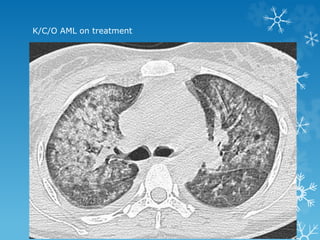

K/C/O AML on treatment

HRCT chest reveals bilateral diffuse GGO with air space consolidation and

subpleural sparing and a few air cysts classical of Pneumocystis jiroveci

pneumonia

Pneumocystis jiroveci pneumonia (PCP)